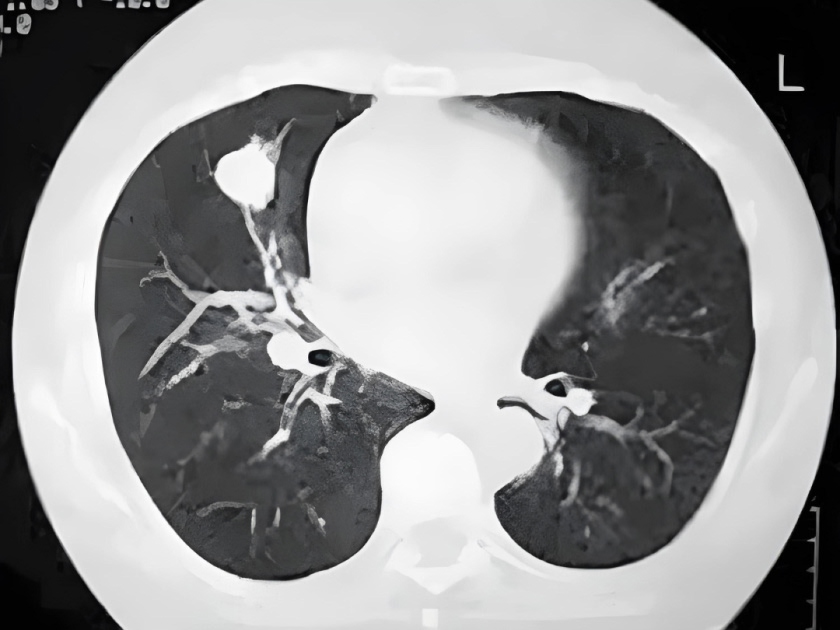

Nódulo pulmonar

Un nódulo pulmonar es una pequeña área anormal que a veces se encuentra durante una tomografía computarizada del tórax. Estas exploraciones se realizan por muchas razones, como parte de la detección del cáncer de pulmón o para examinar los pulmones si tiene síntomas.